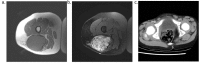

Desmoid tumors are benign soft tissue tumors associated with locally aggressive growth and high rates of morbidity, but they do not metastasize via lymphatic or hematogenous routes. While most of the data on desmoid tumors originates in the adult literature, many of the findings have been applied to the management of pediatric patients. This article discusses the epidemiology, etiology, clinical presentation, pathology, and treatment of this rare tumor in the pediatric population and includes a literature review of the most recent large series of pediatric patients with desmoid tumors.